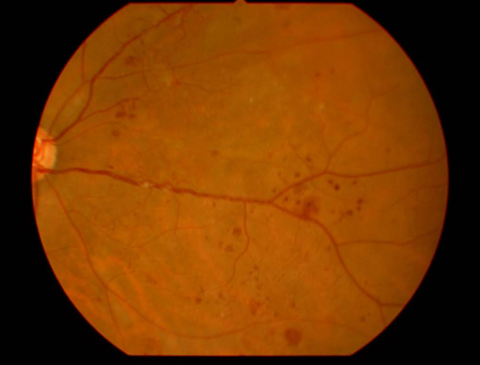

1.単純糖尿病網膜症

| 初期の網膜症 | 高血糖の影響から毛細血管の血管壁が障害され、血管に瘤ができたり、血管壁から血液や血漿成分がしみ出たりすることによって、点状出血や硬性白斑(脂肪やタンパク質の漏出)が生じます。 | この段階では血糖治療、高血圧治療が非常に大切になります。しかし、この段階でも黄斑浮腫が生じている場合には、レーザー治療(網膜光凝固術)や抗VEGF療法の適応になる場合もあります。 |

硬性白斑 |